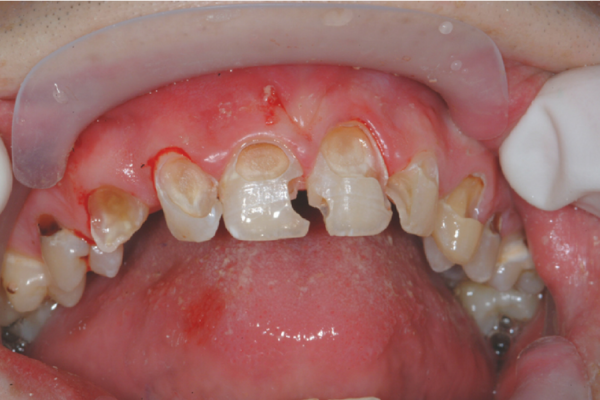

Jangan Anggap Sepele Kerusakan Gigi Anak

Karies gigi pada anak bukan sekadar masalah kecil. Jika dibiarkan, dampaknya bisa luas—mulai dari kesehatan fisik hingga perkembangan belajar dan…